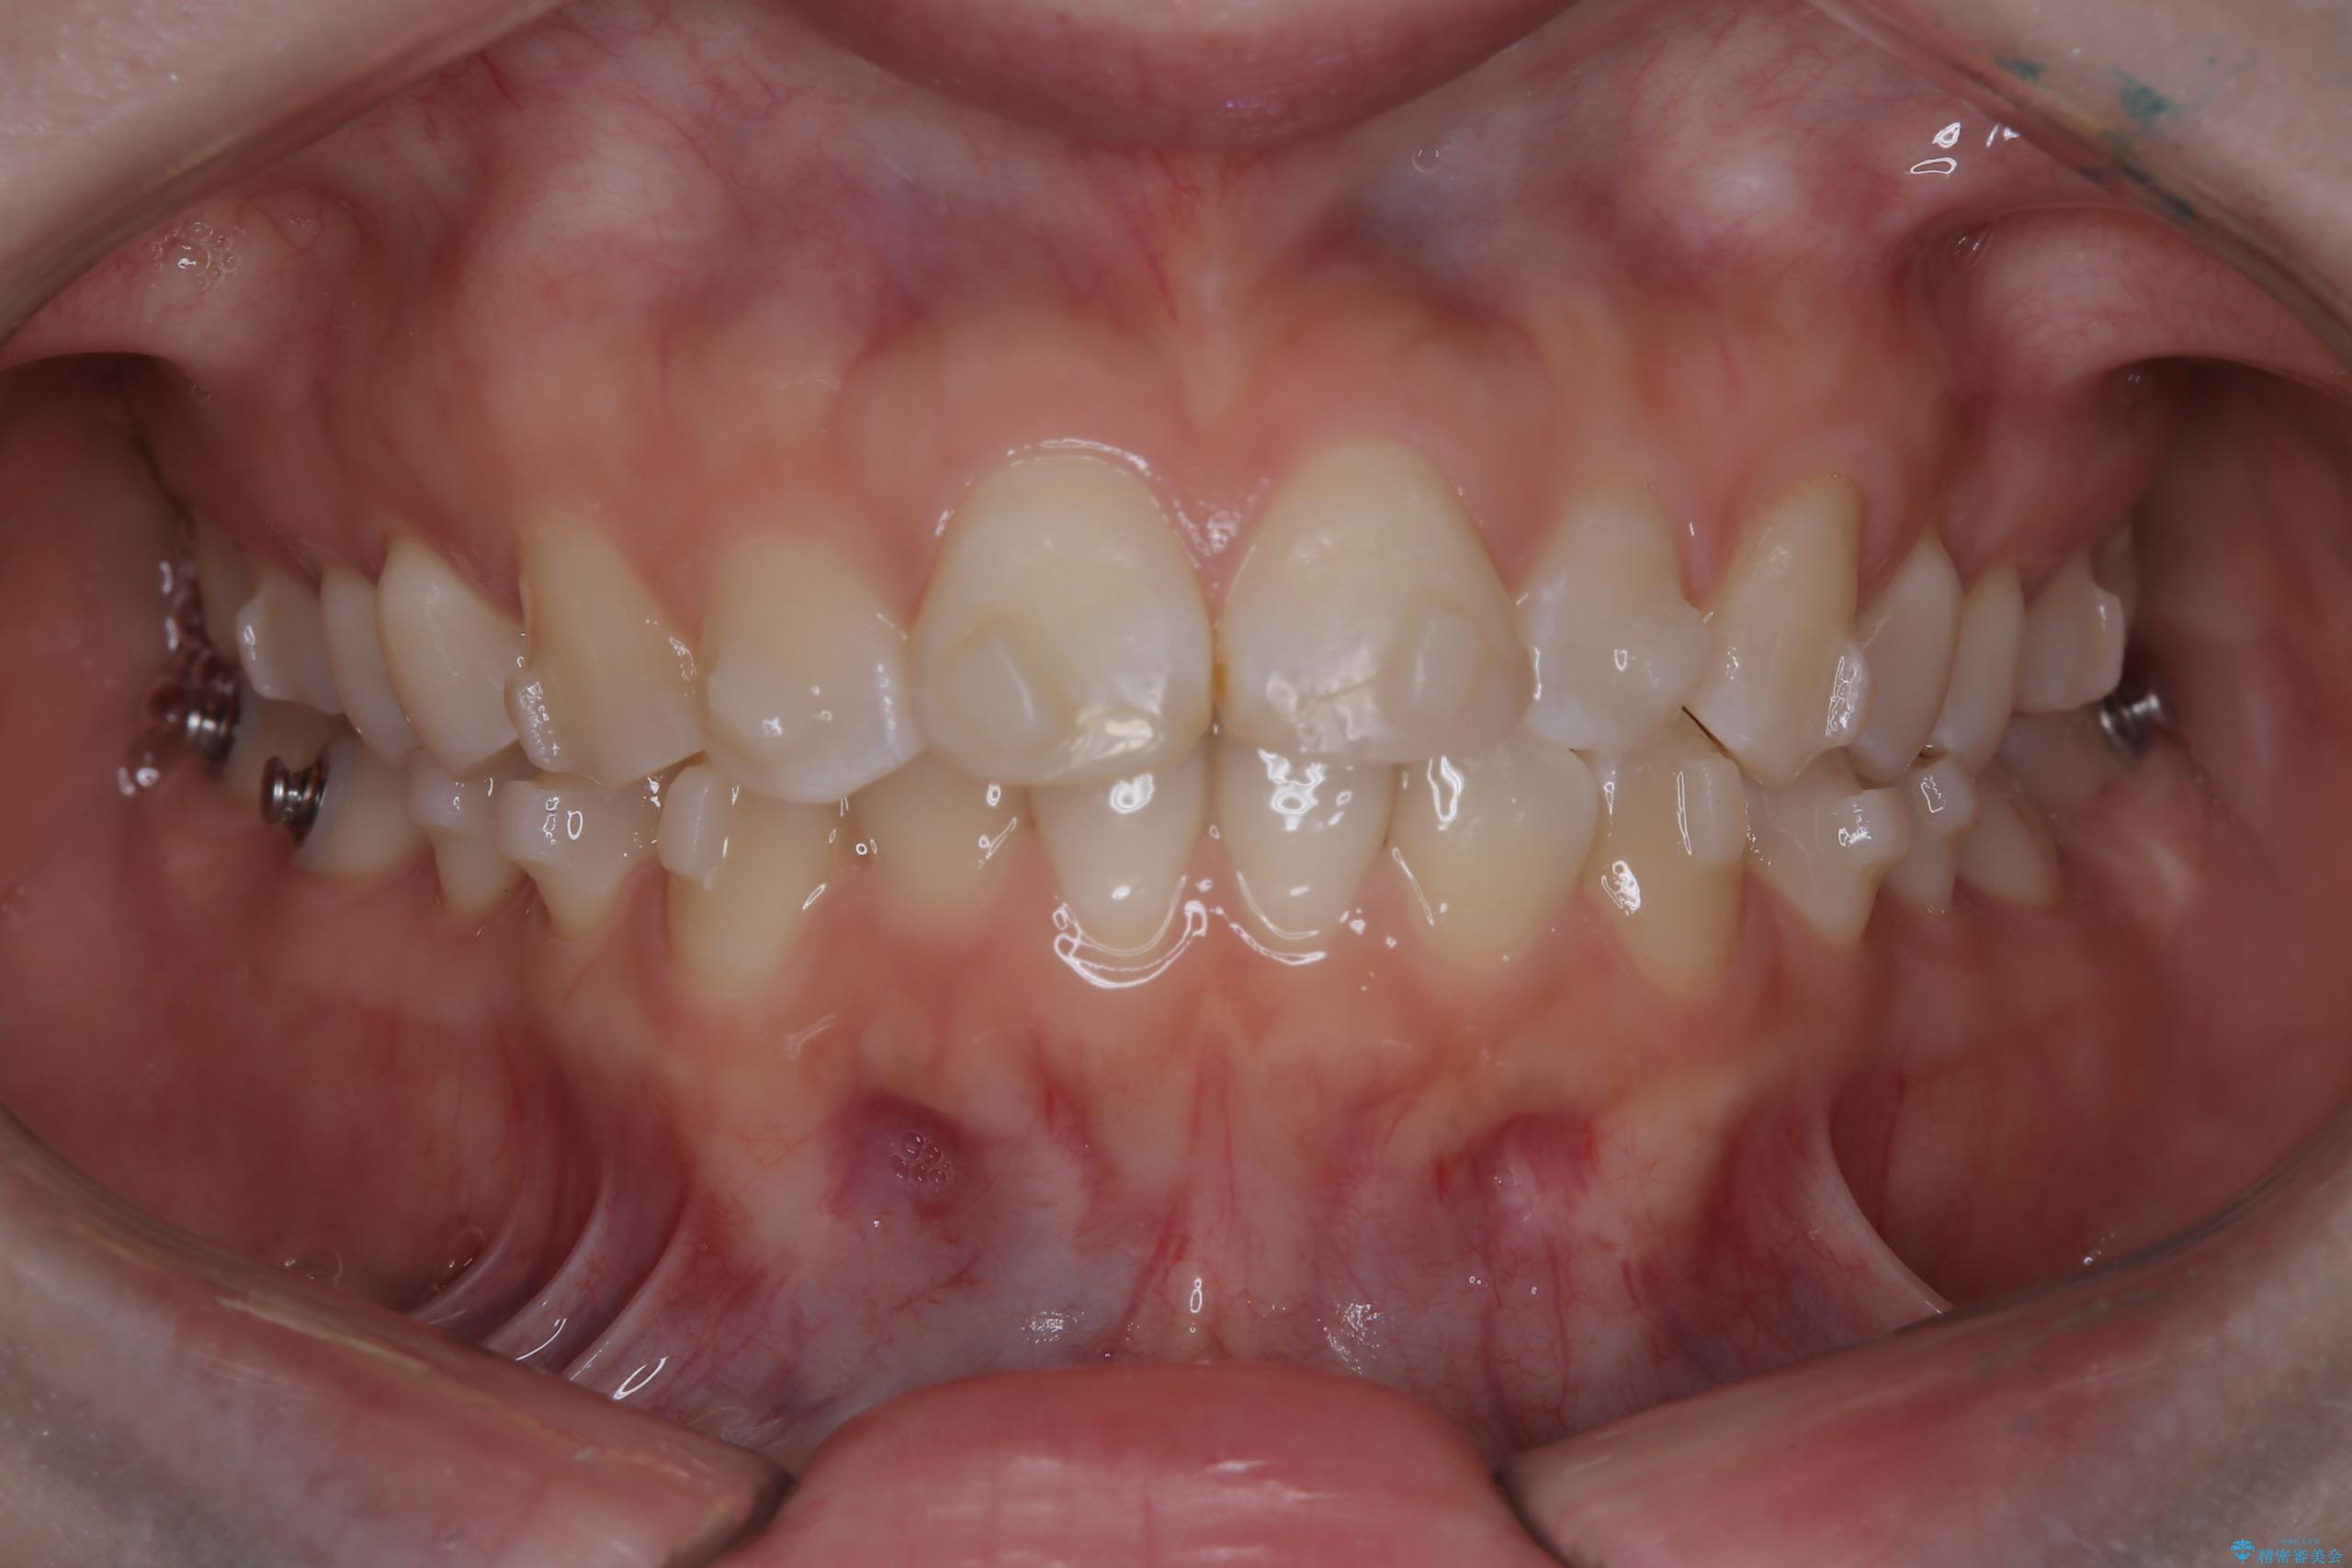

- 前歯のデコボコ(叢生)を気にされてご来院されました。精密な検査の結果、歯が並ぶスペースが不足していることが判明。患者様のご希望から、透明で目立ちにくいインビザライン(マウスピース矯正)による治療計画を立案しました。抜歯を避け、奥歯全体を奥へ動かす遠心移動という方法でスペースを確保し、前歯の叢生を解消することを目指します。

今回の矯正治療では、透明なマウスピース型の装置インビザラインを使用しました。この装置は取り外し可能で、日常生活で目立ちません。治療は、緻密に計算された計画に基づき、段階的に作製されたマウスピースを交換していくことで、奥歯から順に全体を後方へ移動させる遠心移動を実施。これにより、前歯を並べるための十分なスペースが確保され、デコボコが解消されました。抜歯することなく、機能的にも審美的にも整った美しい歯並びを獲得していただけました。